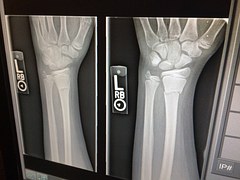

手首の捻挫に対するプライトン固定で驚異の改善